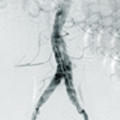

Hercules™ Bifurcated Stent Graft System is indicated for the treatment of infrarenal abdominal aortic aneurysm with proximal aneurysm neck length over 15 mm.